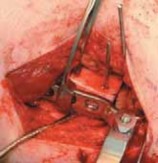

24. The plate is held against the distal segment of the femur using a plate-holding clamp such as the Verbrugge clamp (

TECH FIG 4C

).

25. Before securing the plate, the lower extremity (along with the distal femoral segment) is externally rotated by the desired angle of derotation that can be estimated by the position of the distal pin relative to the proximal pin (

TECH FIG 4D

TECHNIQUES C D E

--- F G HTECH FIG 4 •

(continued)

C. The plate is held against the femur with a plate-holding (Verbrugge) clamp. D. The distal fragment is externally rotated by the desired amount using the two AP pins to judge the angle of correction. E. The plate is secured with cortical screws and the osteotomy is compressed. F. An impacter is used to advance the blade plate to its full depth. G. AP view of the proximal femur. H. Frog-leg lateral view of the proximal femur. cortical screws (3.5 small fragment for the infant and toddler blade plates; 4.5 large fragment screws for the child size and up).

2. At least two of the screws are placed eccentrically to compress the osteotomy site (

TECH FIG 4E

1. The impacter is used to advance the blade plate to its full depth (

TECH FIG 4F

Wound Closure

3. The vastus lateralis is reattached to its origin on the trochanteric ridge with absorbable braided 0 suture so that the entire plate is covered (

TECH FIG 5

). Two or

three tacking sutures are used to reattach the posterior edge of the vastus fascia to the septum.